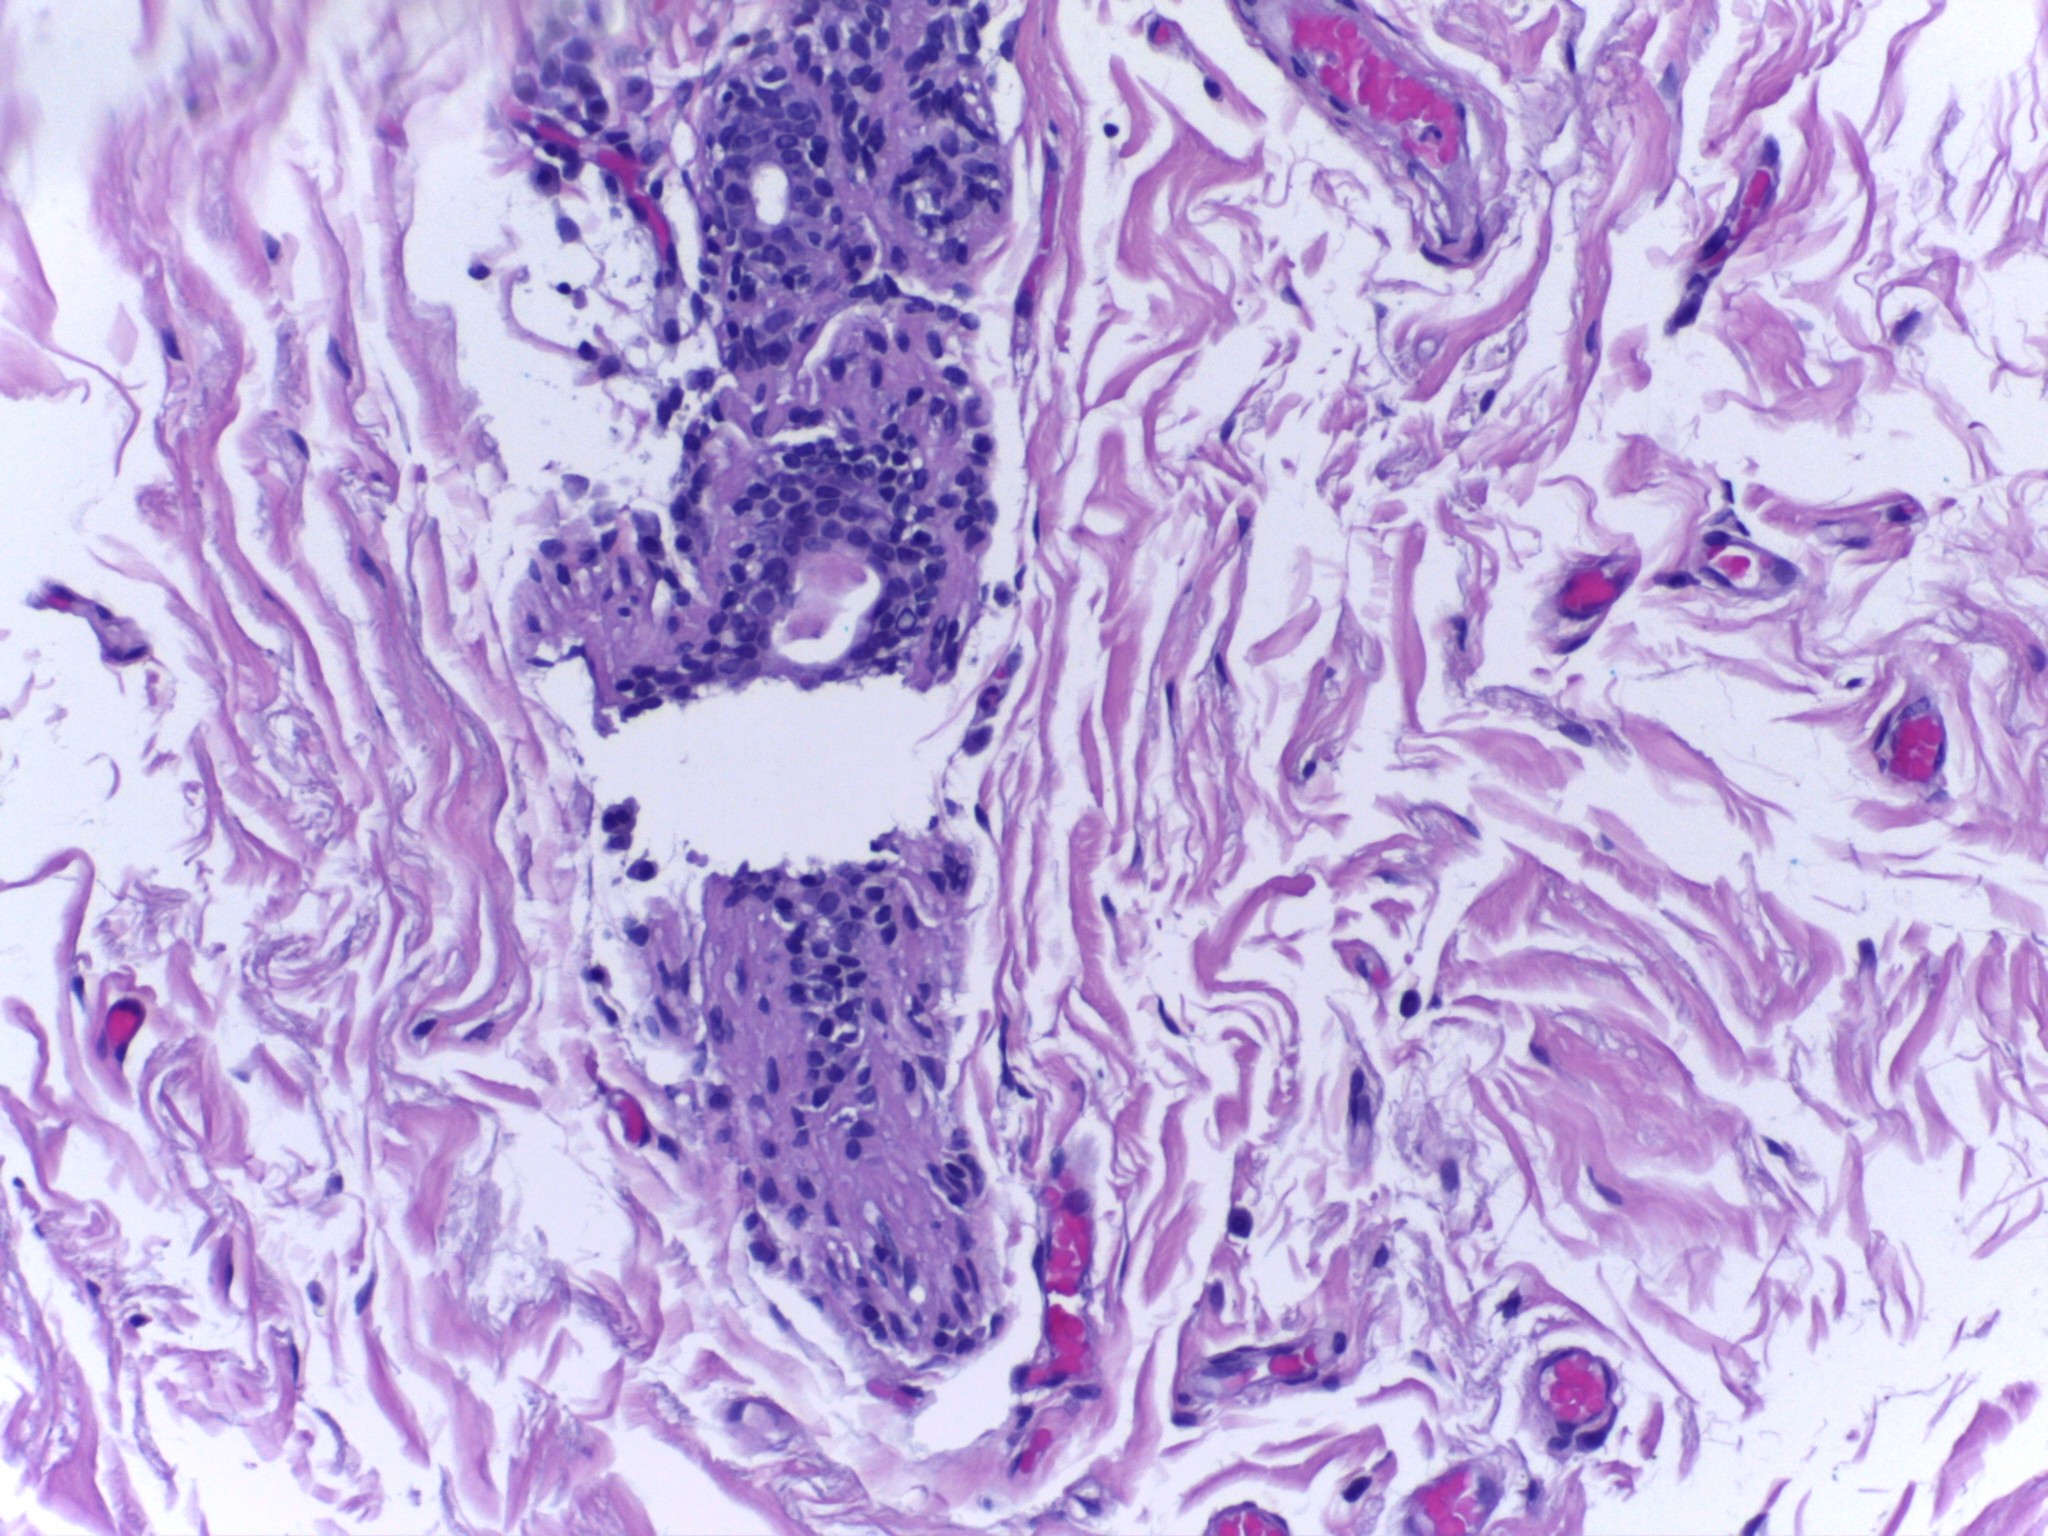

Refer to caption

Normal

Benign

InSitu

Invasive

Figure 5: Images of Breast Cancer Histopathology from the ICIAR2018 Dataset

4.1.2 Dataset

Our network is trained and evaluated on three main datasets: BreakHis b6 , containing 7,909 breast cancer histopathology images (2,429 benign and 5,429 malignant) at 40×, 100×, 200×, and 400× magnifications, each 700×460 pixels; Mini-DDSM b7 , a reduced version of DDSM with approximately 2,000 annotated mammography images detailing lesion locations and diagnoses; and BACH from ICIAR2018 b8 , with 400 HE-stained images in four categories (Normal, Benign, In-situ carcinoma, Invasive carcinoma), each 2048×1536 pixels. Fig. 3, 4, and 5 depict sample images from the BreakHis, Mini-DDSM, and ICIAR2018 datasets. Tables 1, 2, and 3 also present statistical data for these datasets, including sample sizes and class distributions.